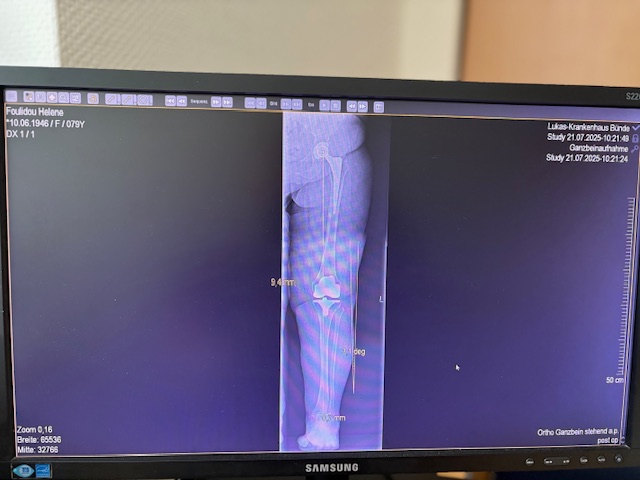

Ο προεγχειρητικός ψηφιακός σχεδιασμός

Πραγματοποιήθηκε σε ειδική ακτινογραφία ολόκληρων των δύο κάτω άκρων. Σε αυτό το ψηφιακό μοντέλο σχεδιάστηκε με ακρίβεια το είδος, το μέγεθος και η ακριβής θέση των προθέσεων, με βάση τα ανατομικά χαρακτηριστικά της ασθενούς.

Ο ψηφιακός σχεδιασμός επιτρέπει απόλυτη εφαρμογή των μοσχευμάτων, ελαχιστοποιώντας τα περιθώρια απόκλισης και εξασφαλίζοντας άριστη ευθυγράμμιση και κινηματική ισορροπία του γόνατος.